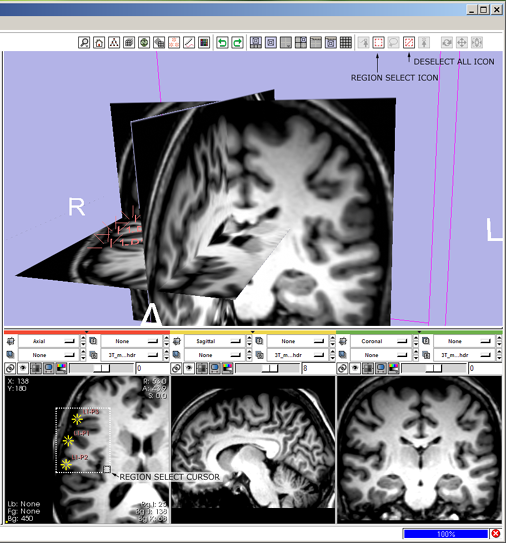

File:SB8.png

SB8.png (506 × 543 pixels, file size: 191 KB, MIME type: image/png)